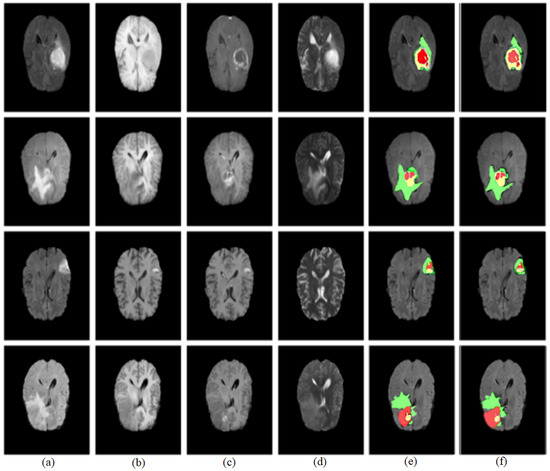

4.6. Qualitative Analysis